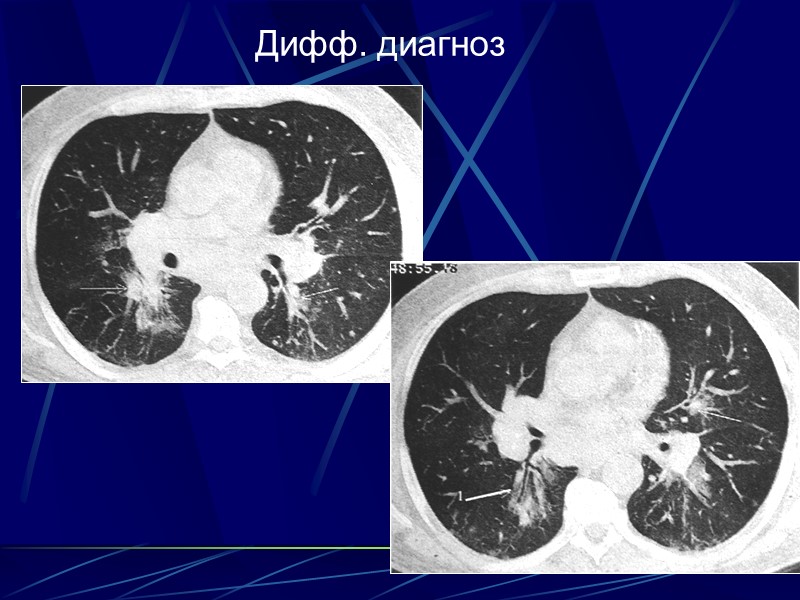

Дифф. диагноз